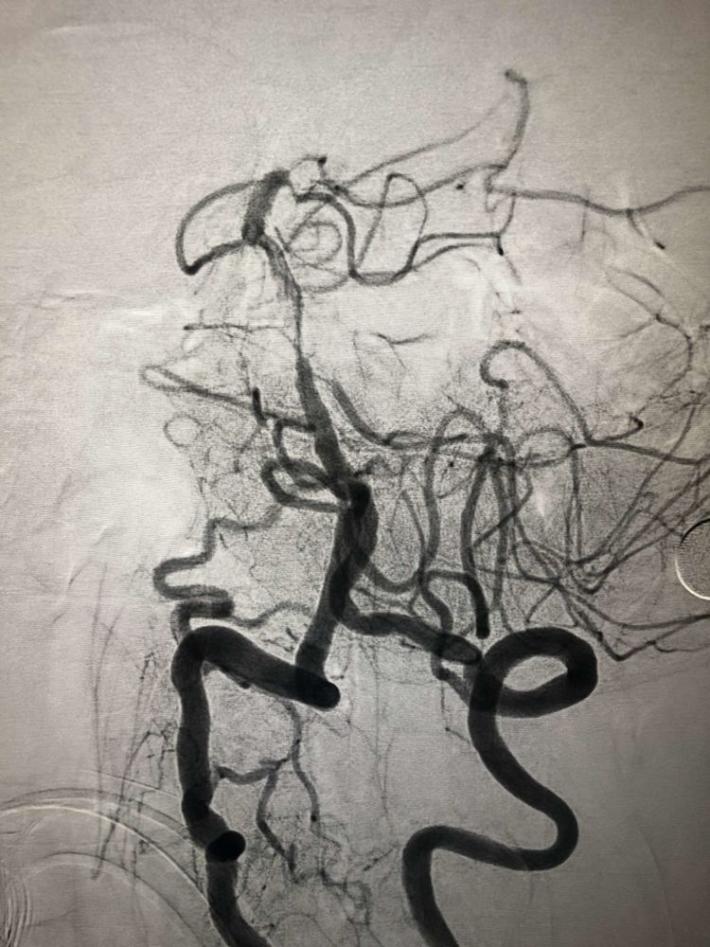

双侧颈内动脉

双侧椎动脉

左侧椎动脉

右侧椎动脉造影:基底动脉中段充盈缺损,基底动脉尖丢失。提示基底动脉中段原位狭窄基础上血栓形成,血栓脱落栓塞基底尖。

微导丝微导管通过闭塞部位,经微导管造影,确认在远端真腔。

一把拉通后,前向血流即刻恢复至3级,双侧小脑上动脉、大脑后动脉、基底动脉尖显影。

现基底动脉残余狭窄约40%,观察20min前向血流3级;斑块累及小脑前下动脉;右侧丘脑出血转化,尽可能避免双抗,综合考虑后放弃急诊支架植入,术后给予盐酸替罗非班泵入维持血流稳定。